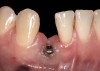

The following case report provides an example of this case scenario: A 24-year-old white male presented with congenitally missing tooth No. 26 restored with a single-tooth cement-retained implant restoration. The implant was placed excessively to the facial aspect of the edentulous site and too shallow, and the periodontal phenotype was thin scalloped (Figure 32). In an effort to mimic the lost midfacial soft tissues, pink ceramics were used as a cosmetic facade. Even though the restoration was not in the esthetic zone, the patient was highly displeased with the esthetic outcome and sought remediation.

The crown and screw-retained custom abutment were removed, and a surgical cover screw was placed into the implant, thereby allowing spontaneous gingival augmentation in situ (Figure 33 and Figure 34). Note that the lingual aspect of the implant site was significantly more coronal than the labial aspect, which was positive because the defect would be limited to a facial–lingual defect. A fixed RBR bridge was cemented on the adjacent teeth and used as a tooth-supported transitional provisional restoration (Figure 35). A few weeks were allotted to let the soft tissue heal and migrate around the cover screw (Figure 36) to see if there would be complete coverage, thereby allowing a soft-tissue augmentation procedure to be performed with primary flap closure as in clinical scenario No. 2. The major obstacle in achieving a positive tissue response was that the implant depth was also deficient because the implant–abutment connection was at the level of the free gingival margin. It was decided that the best treatment option would be to remove the implant. A high-powered reverse-torque device (Fixture Remover Kit, NeoBiotech, www.neobiotechus.com) was used to remove the implant atraumatically (Figure 38 through Figure 41). The implant socket was allowed to heal for several months not unlike an extracted tooth (Figure 42). A new implant was placed in a better position from both a restorative and esthetic perspective (Figure 43), and after a few months of healing, a new crown was made (Figure 44). A satisfactory functional and esthetic result was achieved (Figure 45 and Figure 46) without employing pink porcelain.

Fig 32. A dissatisfied patient presented with significant midfacial recession of implant restoration of tooth No. 26. Pink ceramic material was used unsuccessfully to prosthodontically compensate for the lost midfacial tissue.

Fig 33. Excessive facial angulation of the implant placement shown with an abutment driver in the access screw hole.

Fig 34. A surgical cover screw was placed in an attempt to decoronate the implant and gain soft-tissue coverage in situ.